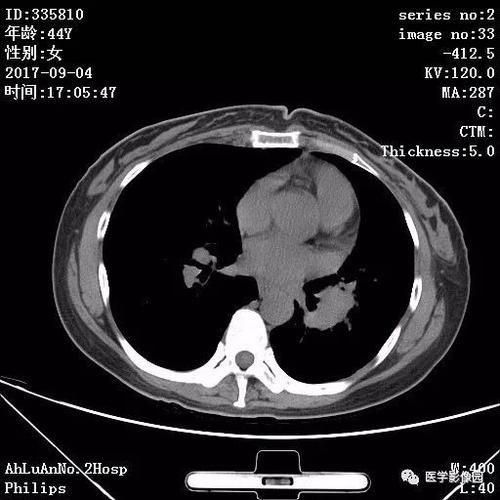

经常有人问,肺结节会不会癌变?了解了以下知识,答案就会变得清晰。肺结节并不等同于癌症,但某些类型的肺结节确实有癌变的风险。通过影像学检查,医生可以评估结节的性质,从而为患者提供更为精确的治疗建议。

影像技术在肺部疾病的诊断中扮演着至关重要的角色。通过正确使用和解读这些技术,我们不仅能够更早地发现疾病,还能够更有效地进行治疗。刘波教授的工作和研究,为我们提供了宝贵的知识和指导,帮助我们更好地理解和应对肺部疾病。让我们持续关注!